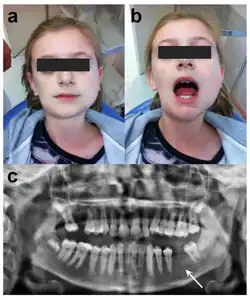

Facial swelling and infection due to Osteomyelitis of Tori

In the cases where osteomyelitis of tori occurs, treatment and management of this condition are adjusted. Instead of a scheduled oral surgery in regular cases where oral tori begin to cause discomfort or symptoms, the patient with osteomyelitis of tori requires prompt medical attention; a patient with this condition must be given intravenous antibiotics and anti-inflammatory drugs, (in some cases) receive a biopsy of the suspected or infected area, and receive surgery and management from an oral and maxillofacial surgeon. This is because osteomyelitis is an inflammatory process of bone and bone marrow which is caused by an infectious organism(s) which result in local bone destruction. These infections can vary from acute to chronic, with acute conditions being sudden and severe and chronic developing slowly and persistently.[14][15]

While the prevalence of osteomyelitis of tori is very rare, it has recently been found possible related to oral tori, and due to its possibility and contributions to existing literature and research related to oral tori, this rare condition of oral tori serves many insights which may enhance the preventative practices of oral tori before it can result in osteomyelitis of tori. The existence and awareness of this condition is also vital for general dentists—and not just oral surgeons—in being able to recognize in order to be able to give proper care, attention, and monitoring to the affected area before it can become infected because osteomyelitis of tori can occur even in cases where oral tori is originally asymptomatic before having an acute onset, which is essential in preventative care.[14][15]